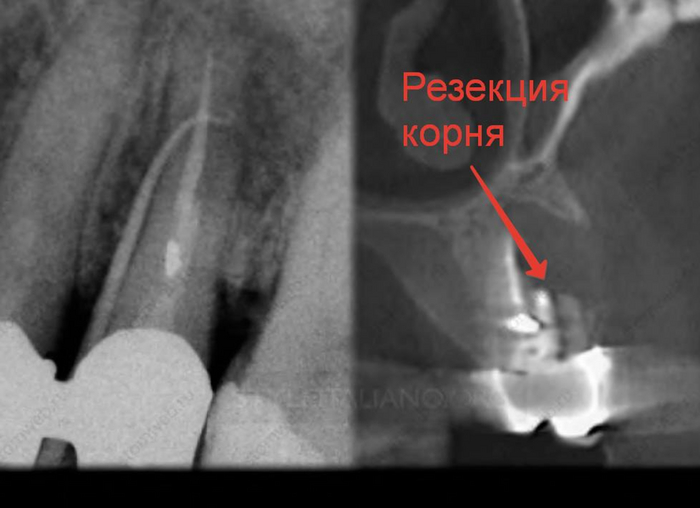

После того, как пациент сделает нормальный трехмерный снимок, с вероятностью 90% мы будем наблюдать один из подобных примеров.

Панорамный снимок- двухмерный

Компьютерная томография- трехмерный

Как вы уже догадались при получении двухмерного изображения трехмерного объекта, его структуры будут накладываться друг на друга. Так как рентген-диагностика заключается в анализе разницы плотности слоев, что выражается на снимках в виде различных оттенков серого, то более плотные слои(белые) могут запросто перекрывать менее плотные(черные), из-за чего точность этой диагностики снижается.

Компьютерная томография «нарезает» объект послойно, позволяя увидеть все структуры под каким угодно углом без искажений. Таким образом мы сможет поставить максимально точный диагноз, определить более точный прогноз зуба, определить расположение будущих и уже установленных имплантатов, определить расположение гайморовой пазухи и нижнего альвеолярного нерва при удалении сложных зубов, определить расположение корней, определить количество каналов в корнях….можно продолжать долго.

Вот ещё примеры.